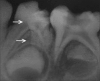

Dental anomalies of number and forms may occur in the primary and permanent dentition. Various terms have been used to describe dental twinning anomalies: Germination, fusion, concrescence, double teeth, conjoined teeth, twinned teeth, geminifusion, and vicinifusion. Fused tooth is a developmental anomaly that is seen more frequently in the primary than the permanent dentition. Double tooth involving deciduous anterior teeth is found mostly in the mandible. Very few cases of nonsyndromic double primary molar have been reported in the literature. The succeeding permanent tooth is often found missing congenitally in the same region. This article reports a very rare unilateral occurrence of an anomalous, primary mandibular first macromolar formed by fusion with a dysmorphic premolar like supernumerary tooth in deciduous dentition period. Instead of agenesis of succedaneous tooth, the double tooth has been succeeded by normally developing mandibular first premolar in the same region.